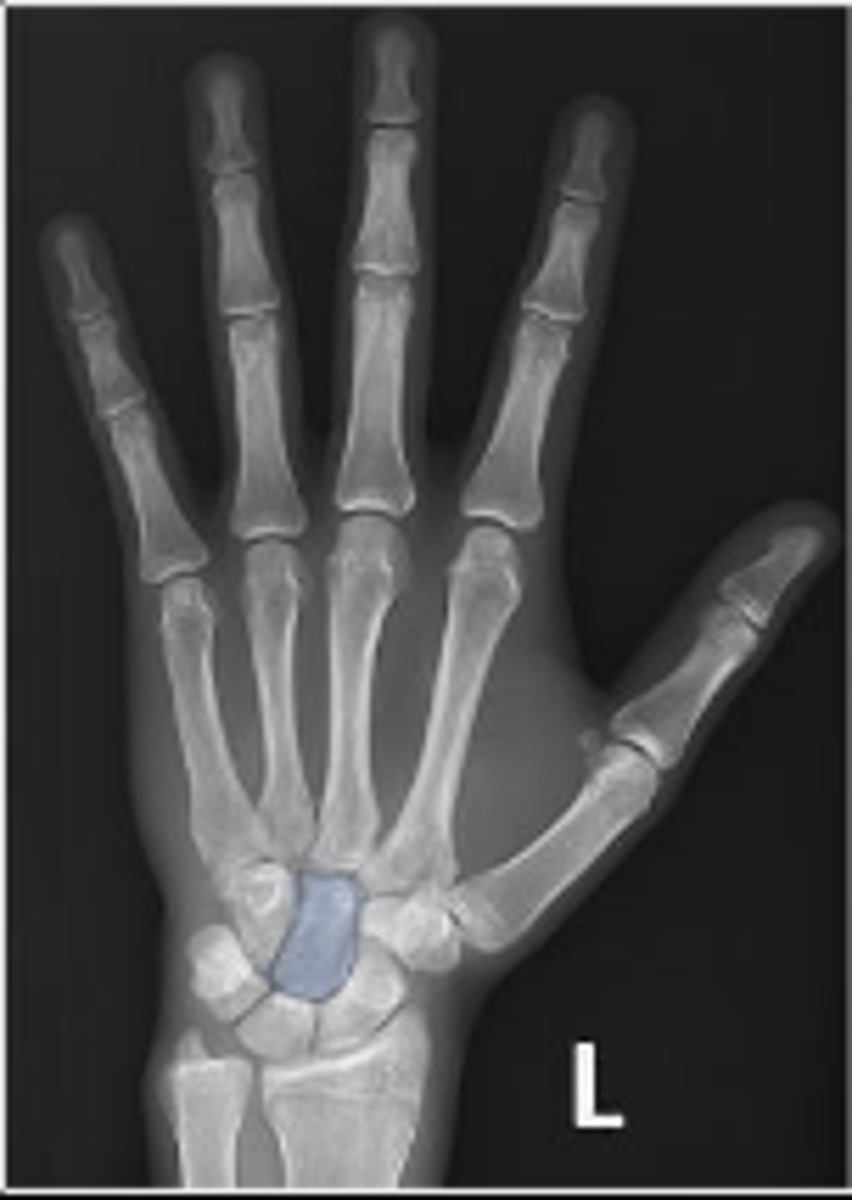

PA of the left hand

What is the name of the radiographic view?